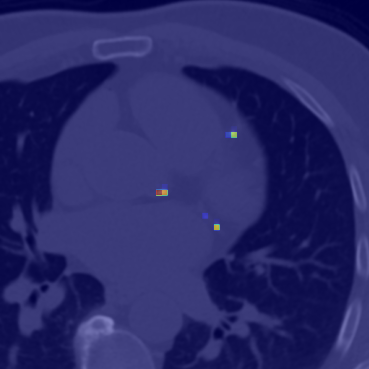

Refer to caption

(a) F1-score of the guided classification model.

(b) F1-score of the non-guded classification model.

Figure 6: Classification results showing the F1-score for both DINO model trained with label-guided approach (a) and standard approach (b).

Comparison of DINO-LG and DINO model via Classification. The comparison is conducted on two different models trained with our label-guided approach and standard DINO model. The confusion matrix for both models are represented in Figure 6 and includes TP (True-Positive), TN (True-Negative), FP (False-Positive) and FN (False-Negative) predictions. The linear classification model is trained for 10101010 epochs, because of the increase in FN predictions. FN predictions indicate that the predicted slices containing calcified areas were incorrectly classified as unannotated or without calcification. Thus, it is crucial keeping FN predictions in low weighted in among other predictions.

The other important prediction type, FP predictions indicate that the slices annotated as non-calcified areas were incorrectly classified as containing calcified areas. Although FP predictions are significantly higher than FN predictions across all predicted slices, it should be noted that segmentation models do not consider FP slices if they do not contain missed or unnoticeable calcified areas. The remaining prediction types of TP and TN represent the slices that were correctly predicted as containing calcified areas and non-calcified areas. The confusion matrix provided for both models reveals that the DINO-LG model has a significant improvement in the prediction of TN and FN. This also demonstrates that the DINO model can be effectively trained for specific tasks.